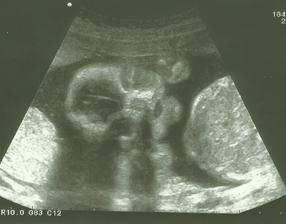

18.12.2012 UTZ bublinka odpovídá 6+4tt a máme srdíčko <3